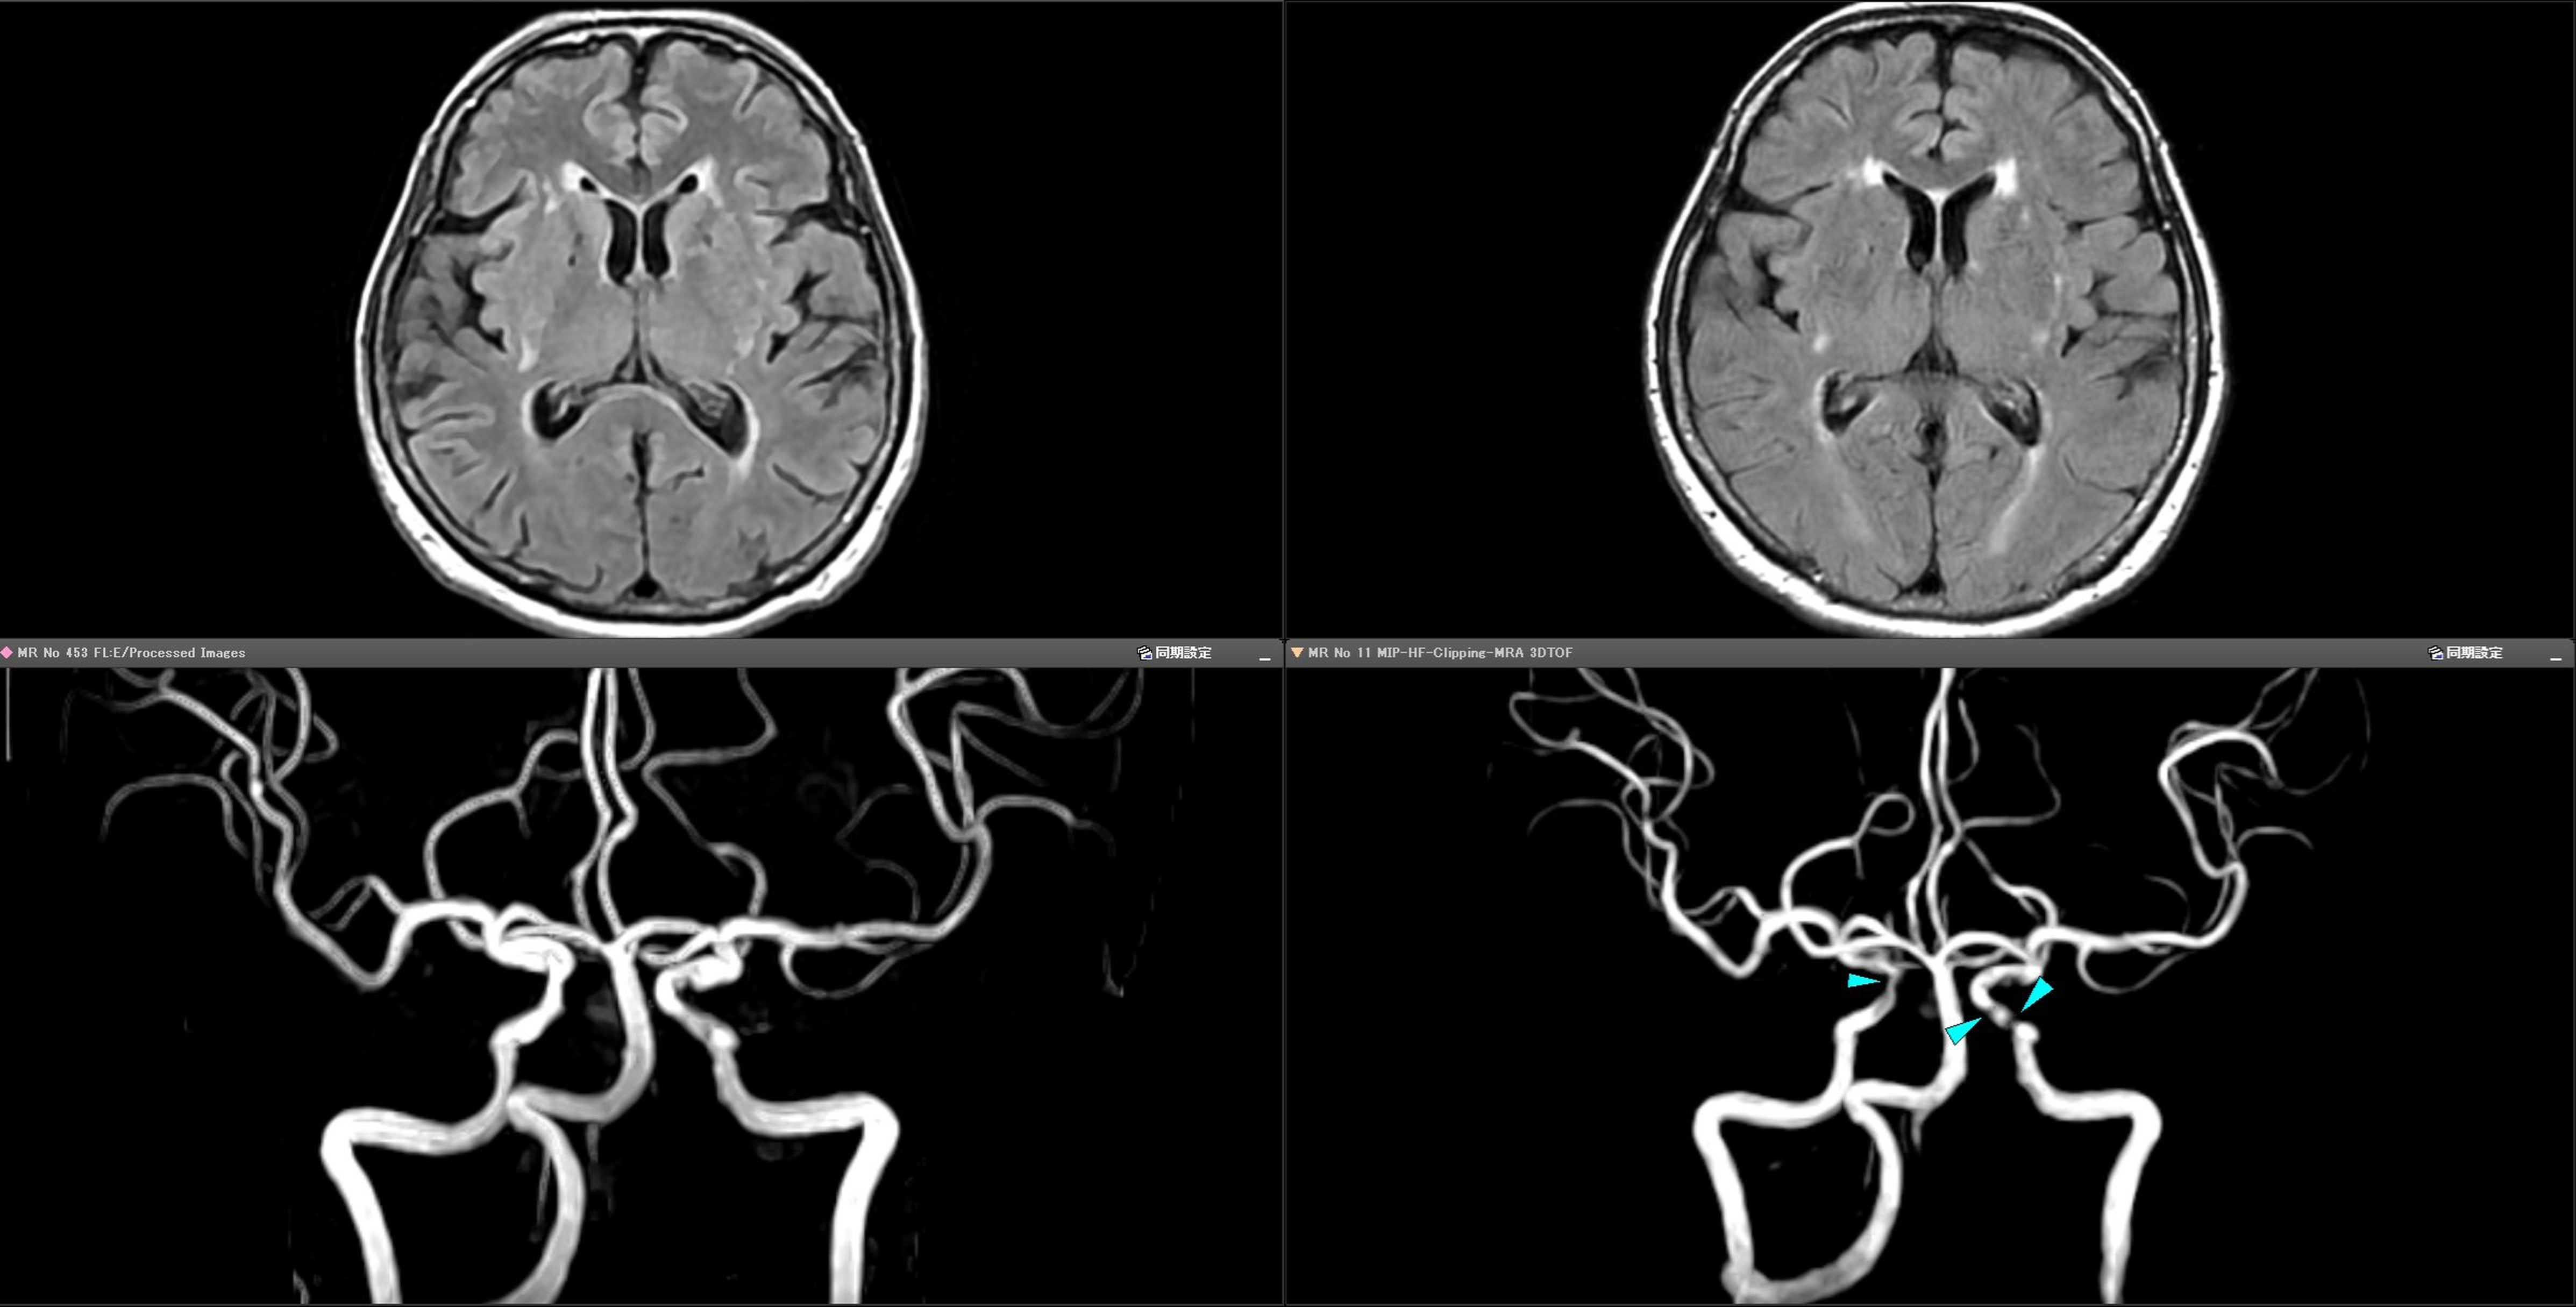

上に示した実際の画像をご覧ください

当院に来られたある患者さんの画像です。左が当院GE SIGNA Explorer、右が国産エントリークラスMRIの画像です。

【上の画像(脳の断面写真)】 左(当院)の方が脳のしわ(脳溝)や表面の境界線がくっきりしているのがわかりますか?右(国産エントリークラス)はどこかぼんやりし画像がざらざらした印象があります。

【下の画像(脳血管の写真)】 右(国産エントリークラス)の画像をよく見てください。水色の矢印が3本あります。この部分の血管描出が不鮮明で、所見の判別が困難です。左(当院)の画像の同じ場所を見てください——血管が明確かつ鮮明に描出されています。